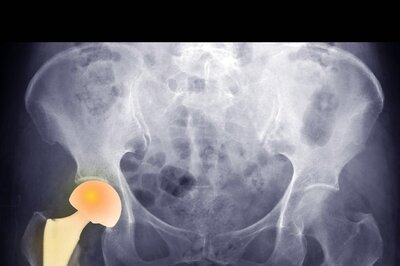

Learn More About Total Hip Arthroplasty and the Function of Robotics in THA

The use of robotics in THA is the newest trending topic for the third decade of this millennium. THA and all associated topics are discussed here by Dr. Samarth Arya, Consultant Orthopaedics, Joint Replacement & Robotic Surgery, Sparsh Hospital, Bengaluru